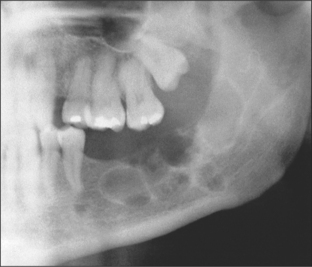

Hard-tissue lesions can arise from odontogenic tissue or from bone. They present a range of diagnoses from developmental lesions such as palatal or mandibular tori or odontomas (see Figs 8.6, 11.13, 11.14) and bony exostoses, to the rarer benign and locally invasive lesions such as ossifying fibroma, ameloblastoma and cementoblastoma.

image

Fig. 8.6 Odontome lying above an unerupted canine and cyst.

Odontomes

These hamartomas (see pathology texts for subclassification) do not continue to grow. They commonly present as a chance radiographic finding, related to delayed eruption of teeth (Fig. 8.6), or as a palpable mass in the alveolar region. Occasionally they cause pain if infected. Radiographs show them to be well-circumscribed, radio-opaque lesions often with a radiolucent margin akin to the periodontal ligament of a tooth.

Clinically they can be considered as malformed supernumerary teeth and treatment should reflect this, with removal recommended if they interfere with tooth eruption or orthodontic tooth movement, or are infected. In the absence of such problems, particularly if there are risks to adjacent structures or the patient has significant co-morbidity, they may be left alone.